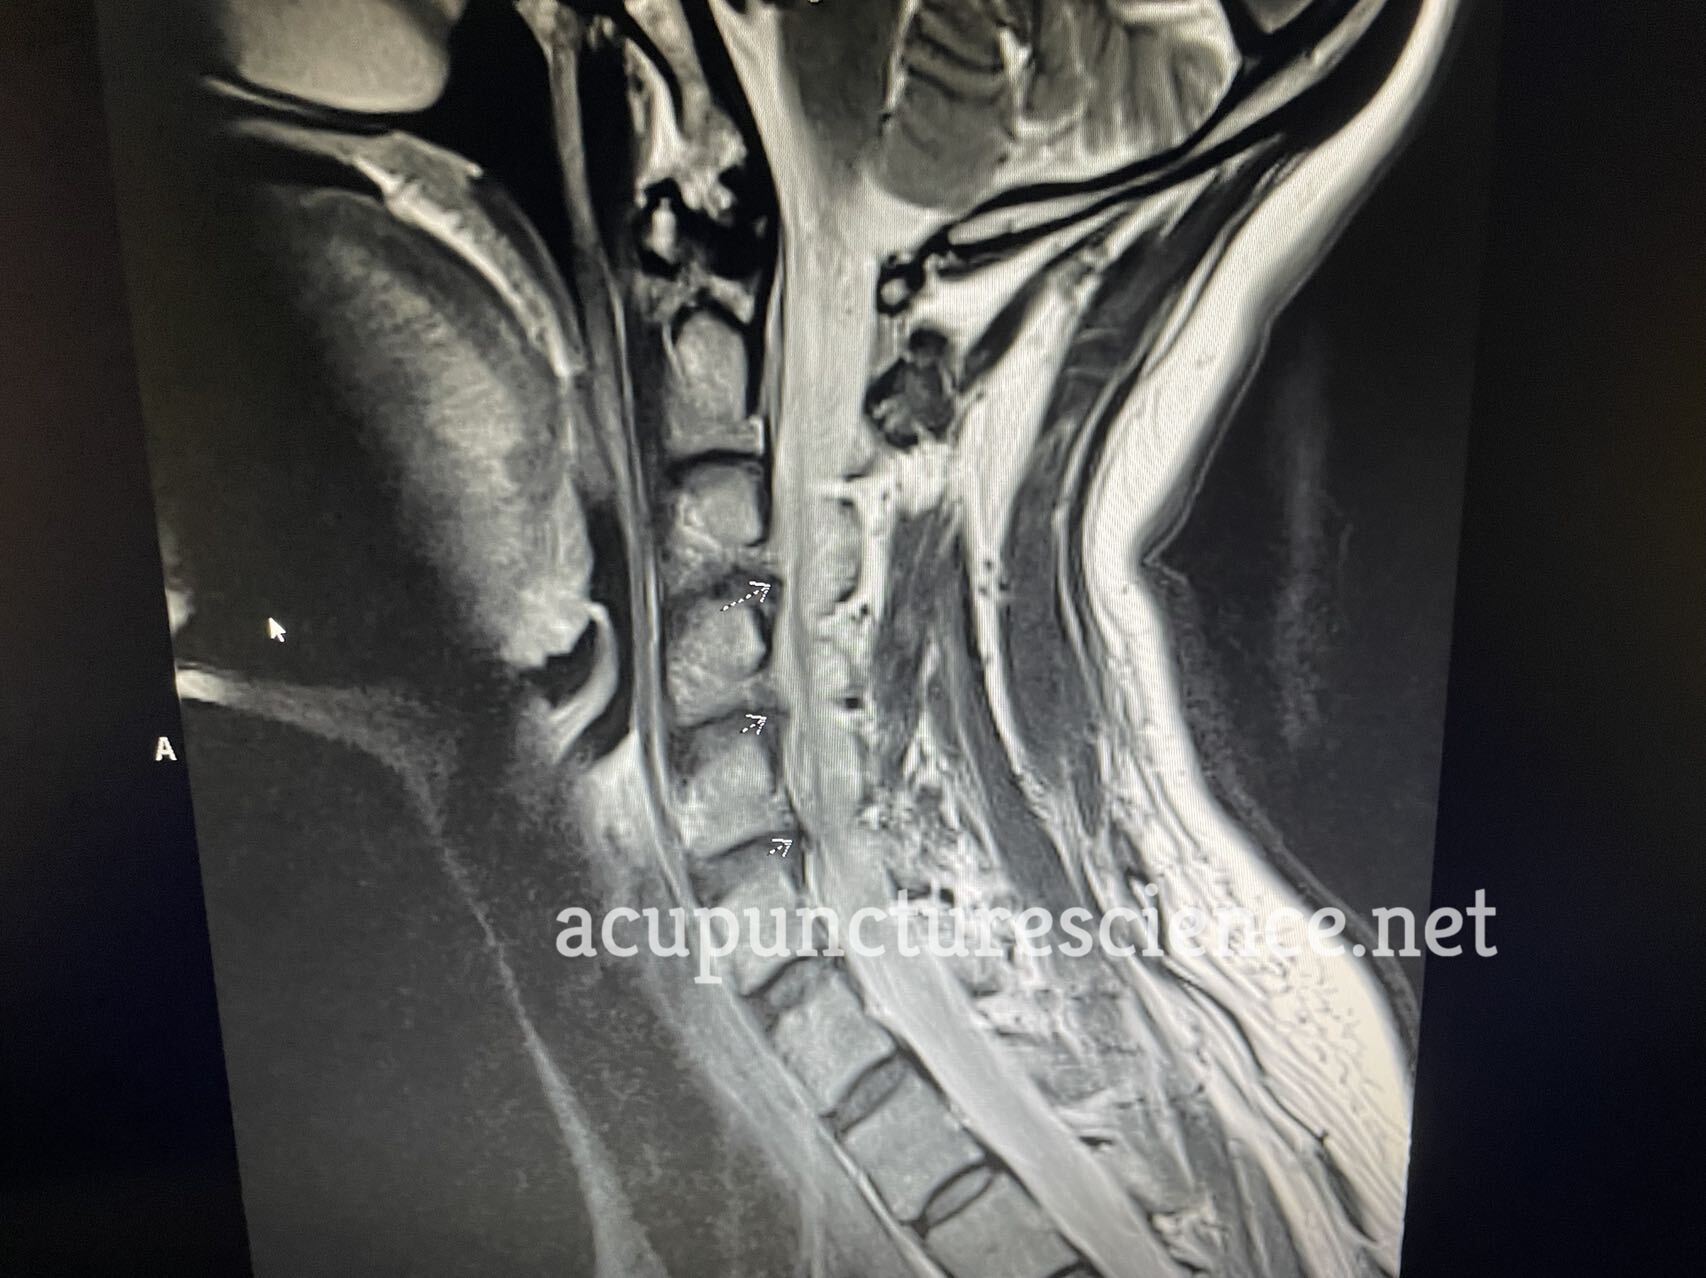

MRI IMPRESSION:

1. Multilevel degenerative disc disease with broad-based disc bulges at C3-C4

through C5-C6 with moderate right neuroforaminal narrowing at C3-C4 and C5-C6.

SPINAL CORD: Normal.

DISCS: Normal.

BONES: Vertebral body height and alignment are normal. Marrow signal is normal.

SOFT TISSUES: Normal.

C2-C3: No canal or foraminal stenosis.

C3-C4: Broad-based disc osteophyte complex is seen with moderate right and mild

left neuroforaminal narrowing. No central canal stenosis.

C4-C5: Broad-based disc osteophyte complex is seen without significant

neuroforaminal narrowing. No central canal stenosis.

C5-C6: Broad-based disc osteophyte complex is seen with moderate right and mild

C6-C7: No canal or foraminal stenosis.

C7-T1: No canal or foraminal stenosis.